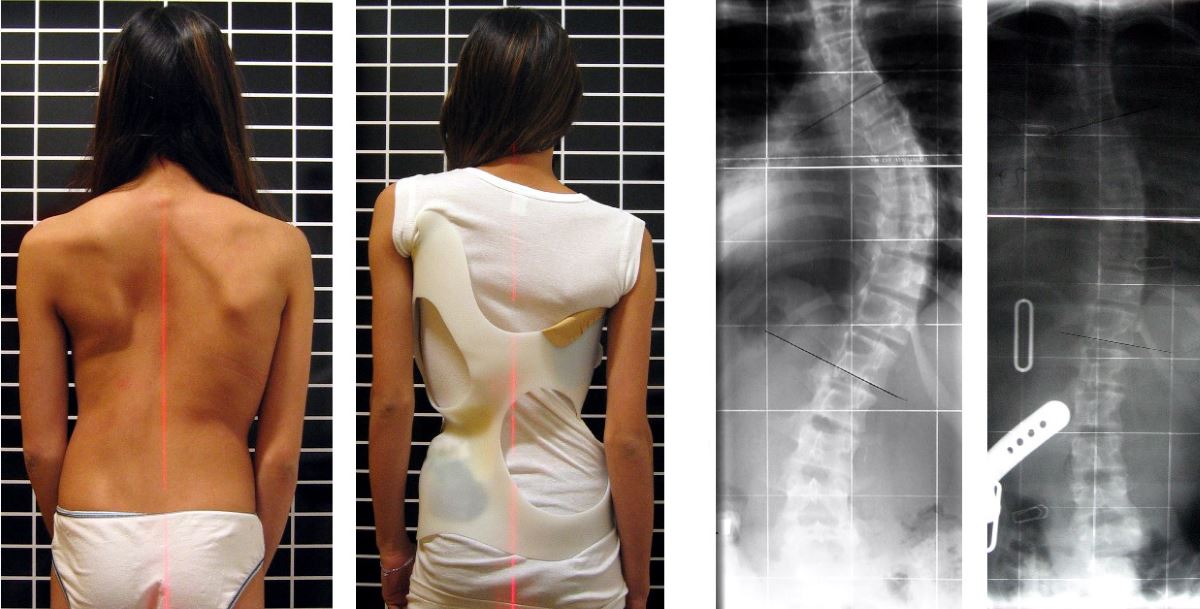

Искривление позвоночника у девушек

Полный размер 1200 × 609 пикселей Искривление позвоночника